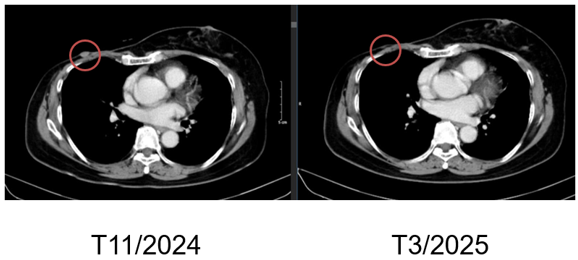

Hình 1. Hình ảnh chụp CT ngực trước điều trị: Tổn thương tái phát thành ngực

Hình 4. Hình ảnh chụp CT ngực trước và sau điều trị: Tổn thương tái phát thành ngực

+ Thành ngực phải có nốt đặc đường kính 5mm – theo dõi tổn thương tái phát